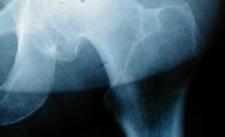

Individuals with severe arthritis often find refuge in hip replacement devices, orthopedic experts say, affirming the importance of certain solutions to facilitate movement. Hip replacement is a surgical procedure in which the damaged hip joint is removed and is replaced by artificial parts known as prosthesis. Elder individuals are often the ones who undergo hip replacement due to worn-out hip joints. However, the US Food and Drug Administration (FDA) have advice the